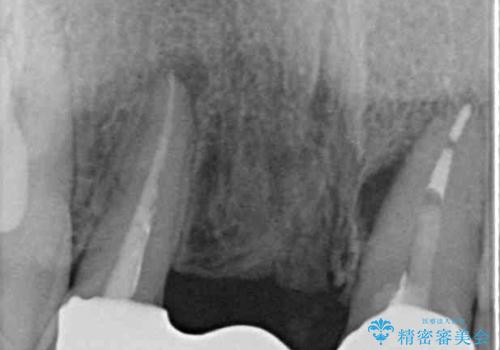

- 矯正治療中に装着していた仮歯を綺麗にしたいとのことで来院された患者様です。

小学生の頃に歯をぶつけて抜歯となりブリッジを装着したそうですが、その後矯正治療を行うに当たりブリッジを切断したとのことでした。

残っている歯根の状態はあまり良くなく、長期的な予後を考えると抜歯を検討するべきでしたが、20代前半という年齢を考え、オールセラミックブリッジにて補綴治療を行うこととしました。